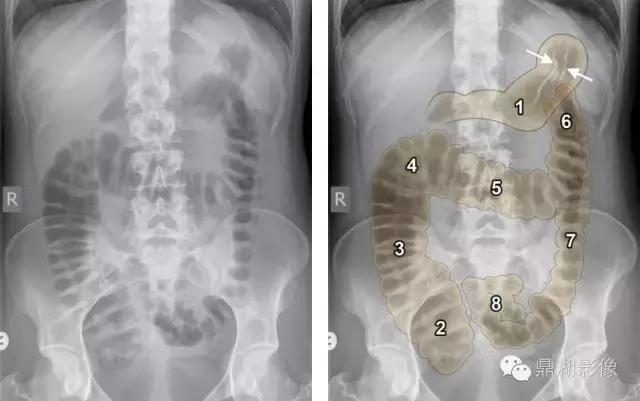

1.胃,注意肠胃壁皱褶(白色箭头) 2.盲肠 3.升结肠 4.肝曲 5.横结肠 6.脾曲 7.降结肠 8.乙状结肠